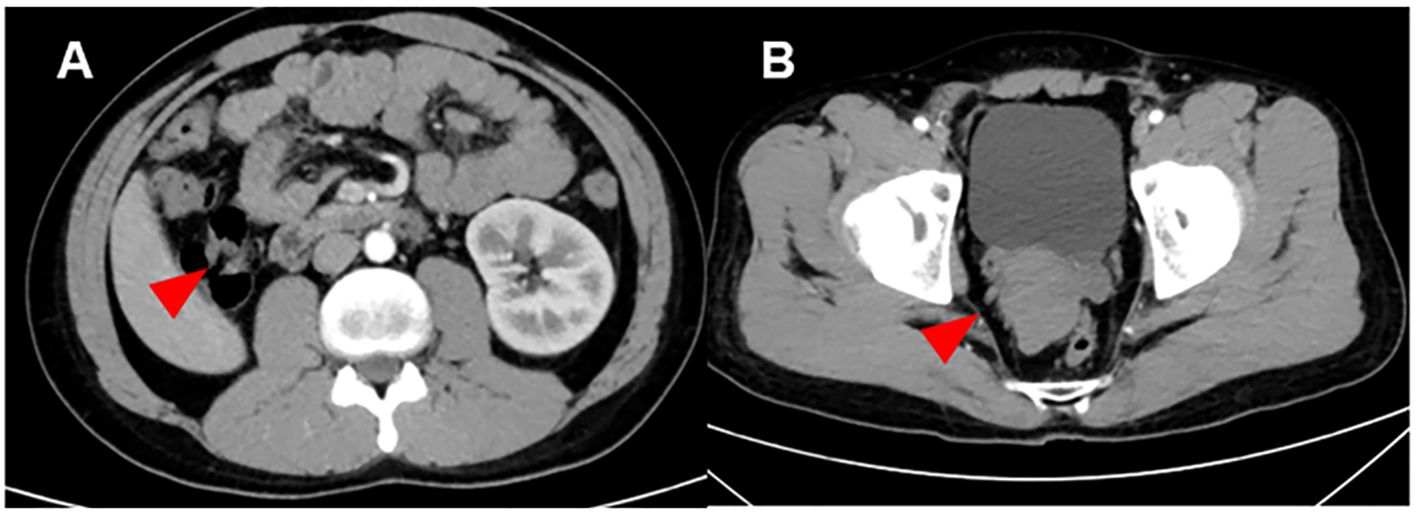

Abstract Background: Zinner syndrome is a rare congenital disorder of the urogenital system. In current reports, cases of Zinner syndrome complicated by malignant tumors are even rarer. Case Description: We reported a 26-year-old male with Zinner syndrome complicated by testicular embryonal carcinoma and retroperitoneal lymph node metastasis. He received orchiectomy, chemotherapy and a retroperitoneal lymph node dissection with favorable response. Conclusions: As suggested by this rare case, Zinner syndrome may be bound up with genitourinary malignancy tumor. When diagnosing congenital disorders of the urinary system, it is essential for clinicians to take into consideration potential complications. More importantly, it is also paramount to account for the similarities and differences in diagnosis and treatment between comorbid and isolated conditions.